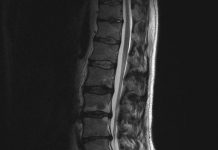

Fixeren met schroeven bij vernauwde wervelkanaal vaak overbodig

De gangbare operatieve behandeling bij patiënten met een vernauwing in het wervelkanaal (lumbale stenose) moet worden herzien. Dat blijkt uit Zweeds en Amerikaans onderzoek....